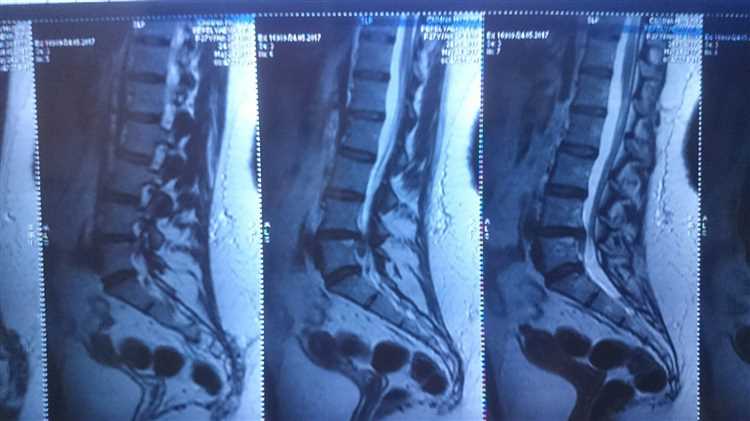

Грыжа – это состояние, при котором орган или часть органа выходит за пределы своей нормальной анатомической позиции, часто через слабое место в мышечной стенке. В зависимости от типа и расположения грыжи, она может вызывать боли, дискомфорт и ограничивать физическую активность. Например, позвоночная грыжа может приводить к сильным болям в спине и ногах, что затрудняет выполнение физической работы. Важно обратиться к врачу для определения степени тяжести состояния и получения рекомендаций по продолжению трудовой деятельности.

Можно ли работать физически при грыже позвоночника?

Физические нагрузки при грыже позвоночника. Следует избегать нагрузок, если после них появляется дискомфорт или боль.

Какая работа противопоказана при грыже позвоночника?

При грыже позвоночника противопоказаны работы, связанные с тяжелыми физическими нагрузками, поднятием и переноской тяжестей, длительным сидением или стоянием, а также с резкими движениями и наклонами. Это может усугубить состояние и привести к осложнениям.